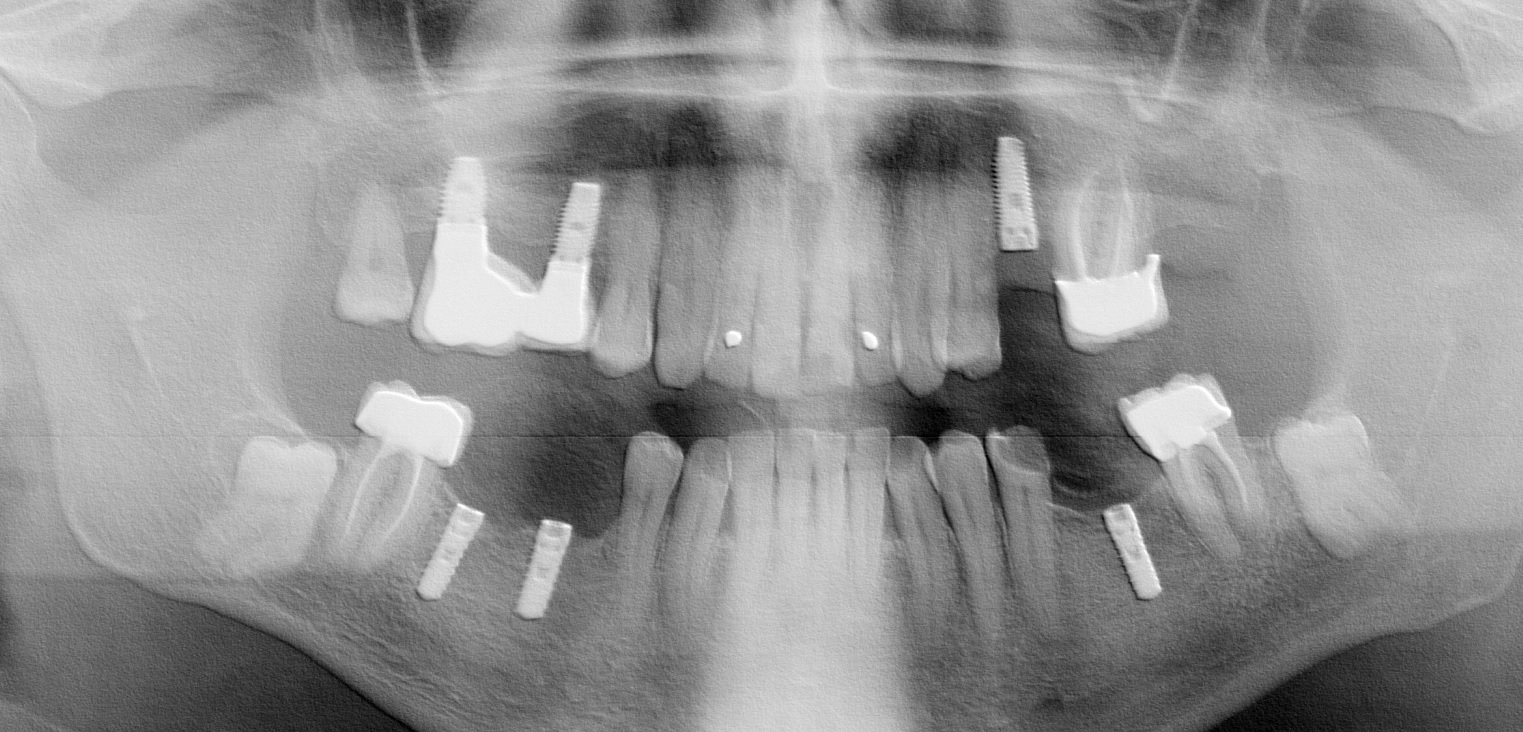

El paciente acude a la consulta por problemas en sus prótesis sobre implantes, colocadas en los cuatro cuadrantes. No sabemos la fecha de colocación de los implantes. El implante en [...]